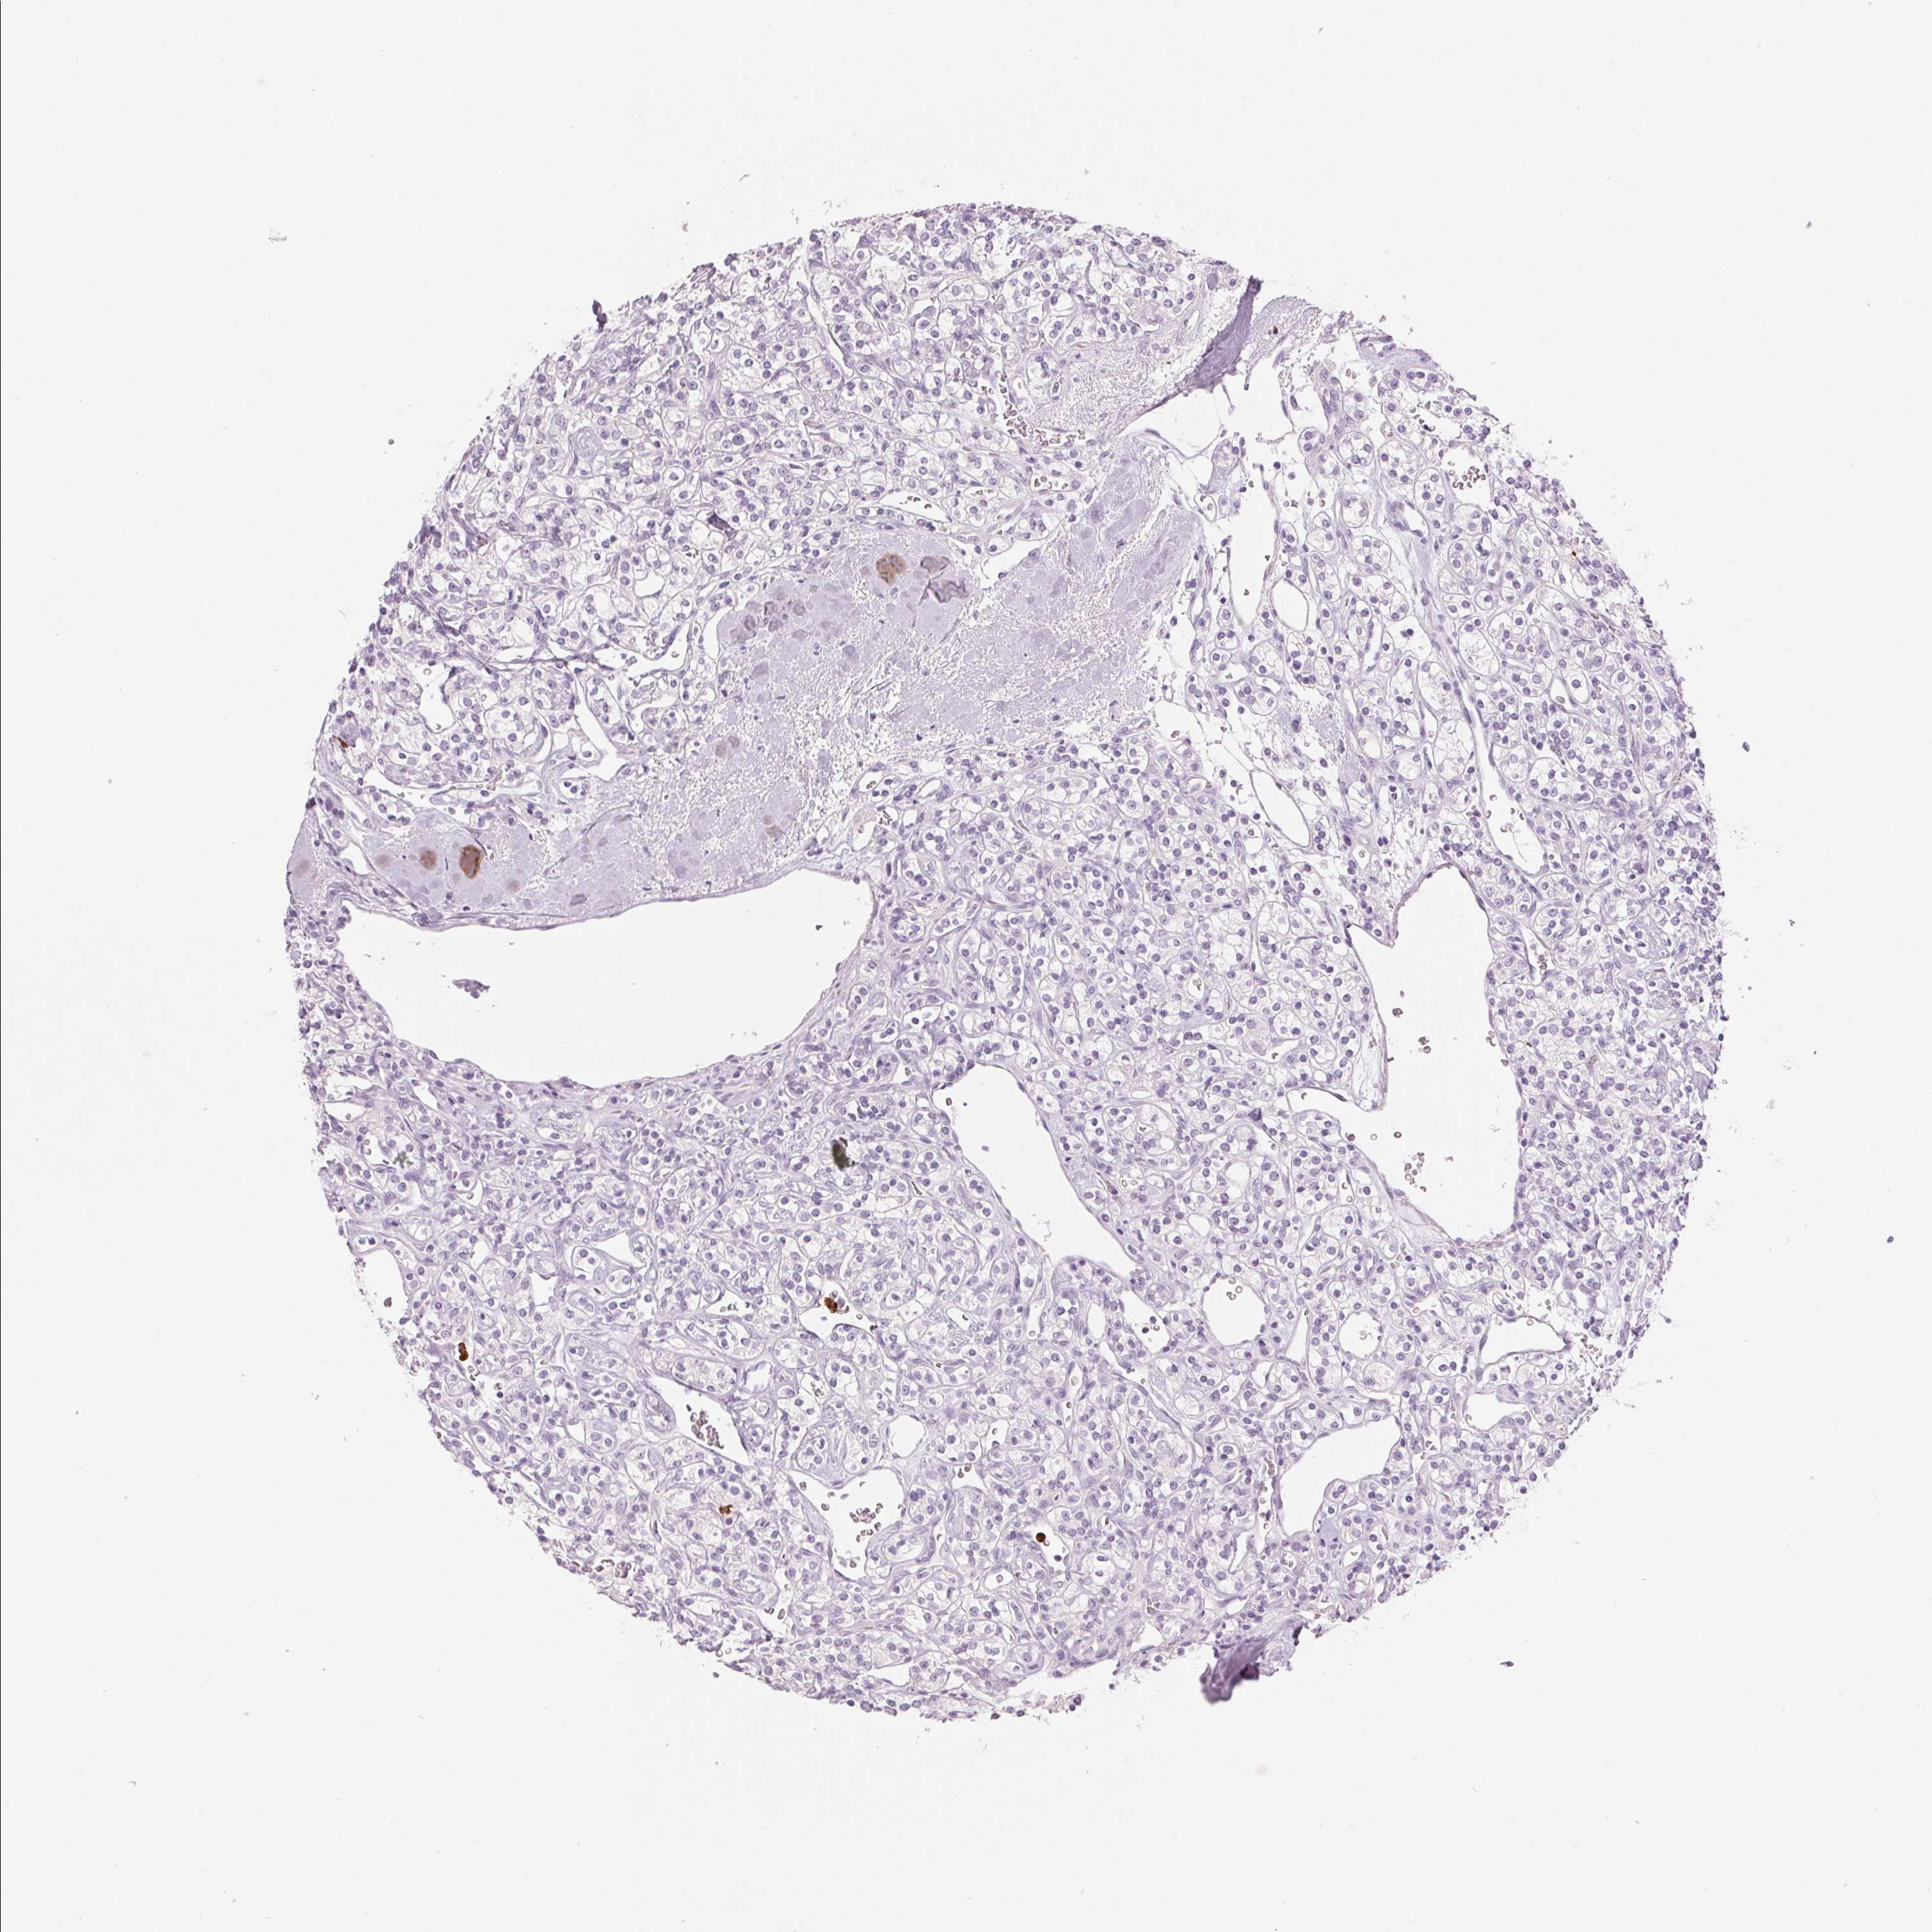

KIDNEY RENAL PAPILLARY CELL CARCINOMA (TCGA) - Interactive survival scatter ploti

The Survival Scatter plot shows the clinical status (i.e. dead or alive) for all individuals in the patient cohort, based on the same data that underlies the corresponding Kaplan-Meier plots. Patients that are alive at last time for follow-up are shown in blue and patients who have died during the study are shown in red.

The x-axis shows the expression levels (FPKM) of the investigated gene in the tumor tissue at the time of diagnosis. The y-axis shows the follow-up time after diagnosis (years). Both axes are complimented with kernel density curves demonstrating the data density over the axes. The top density plot shows the expression levels (FPKM) distribution among dead (red) and alive patients (blue). The right density plot shows the data density of the survived years of dead patients with high and low expression levels respectively, stratified using the cutoff indicated by the vertical dashed line through the Survival Scatter plot. This cutoff is automatically defined based on the FPKM cutoff that minimizes the p-score. The cutoff can be changed by dragging the vertical line or by entering a cutoff value in the square labeled "Current cut-off".

Under the Survival Scatter plot the p-score landscape (black curve; left axis) is shown together with dead median separation (red curve; right axis). Dead median separation is the difference in median mRNA expression between patients who have died with high and low expression, respectively. It is calculated as follows: median FPKM expression of dead patients with high expression - median FPKM expression of dead patients with low expression. This is intended to aid the user in visually exploring custom cutoffs and the associated p-scores and dead median separation.

Individual patient data is displayed and can be filtered by clicking on one or more of the category buttons on the top of the page. Categories describing expression level and patient information include: high, low, alive, dead, female, male and tumor stages. The scale of the x-axis can be toggled between linear and log-scale by clicking on the "x log" button. Mouse-over function shows TCGA ID, patient information and mRNA expression (FPKM) for each patient.

& Survival analysisi

Kaplan-Meier plots summarize results from analysis of correlation between mRNA expression level and patient survival. Patients were divided based on level of expression into one of the two groups "low" (under cut off) or "high" (over cut off). X-axis shows time for survival (years) and y-axis shows the probability of survival, where 1.0 corresponds to 100 percent.

KLK7 is not prognostic in Kidney Renal Papillary Cell Carcinoma (TCGA)